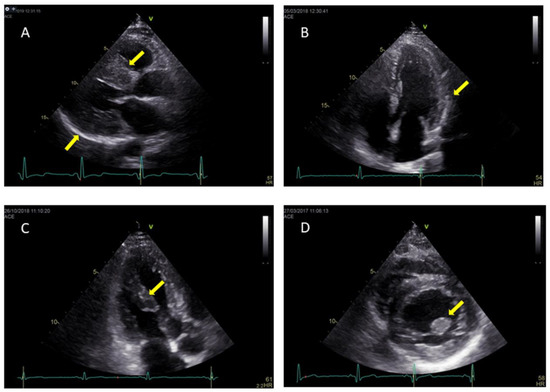

- Pieroni, M.; Chimenti, C.; De Cobelli, F.; Morgante, E.; Del Maschio, A.; Gaudio, C.; Russo, M.A.; Frustaci, A. Fabry’s disease cardiomyopathy: Echocardiographicdetection of endomyocardial glycosphingolipid compartmentalization. J. Am. Coll. Cardiol. 2006, 47, 1663–1671. [Google Scholar] [CrossRef] [PubMed]

- Kounas, S.; Demetrescu, C.; Pantazis, A.A.; Keren, A.; Lee, P.J.; Hughes, D.; Mehta, A.; Elliott, P.M. The binary endocardial appearance is a poor discriminator of Anderson-Fabry disease from familial hypertrophic cardiomyopathy. J. Am. Coll. Cardiol. 2008, 51, 2058–2061. [Google Scholar] [CrossRef] [PubMed][Green Version]

- Mundigler, G.; Gaggl, M.; Heinze, G.; Graf, S.; Zehetgruber, M.; Lajic, N.; Voigtländer, T.; Mannhalter, C.; Sunder-Plassmann, R.; Paschke, E.; et al. The endocardial binary appearance (‘binary sign’) is an unreliable marker for echocardiographic detection of Fabry disease in patients with left ventricularhypertrophy. Eur. J. Echocardiogr. 2011, 12, 744–749. [Google Scholar] [CrossRef] [PubMed][Green Version]

- Niemann, M.; Liu, D.; Hu, K.; Herrmann, S.; Breunig, F.; Strotmann, J.; Störk, S.; Voelker, W.; Ertl, G.; Wanner, C.; et al. Prominent papillary muscles in Fabry disease: Adiagnostic marker? Ultrasound Med. Biol. 2011, 37, 37–43. [Google Scholar] [CrossRef] [PubMed]

| Binary Sign | -Hyperechogenic endocardial surface adjacent to a hypoechogenic subendocardial layer | -Once considered pathognomonic -Overall low sensitivity and specificity |

| Prominent Papillary Muscles | -Papillary muscle thickening and hyperechogenicity | -Late sign, not for screening purposes |